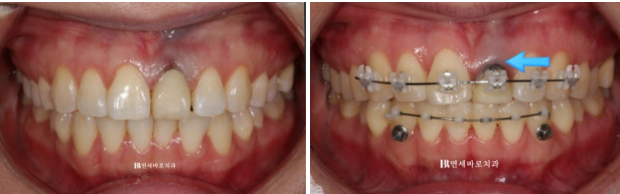

윗니에는 치아 뿌리까지 움직이기 수월하도록 클리피씨 장치를, 배열이 삐뚠 아랫니에는 부분교정용 MTA 장치를 붙여서 교정을 시작했습니다.

22.10~23.04

부러진 치아에 임시치아를 씌운 상태로 클리피씨를 붙이고 교정을 진행합니다.

보통 치아를 잇몸뼈로부터 정출 시키면 잇몸도 같이 따라 내려옵니다.

그래서 6개월 후 사진의 파란 화살표를 보면 잇몸이 치아와 함께 아래로 많이 자라 내려오면서 처음에 비해 치아가 절반정도로 짧아져 보입니다.